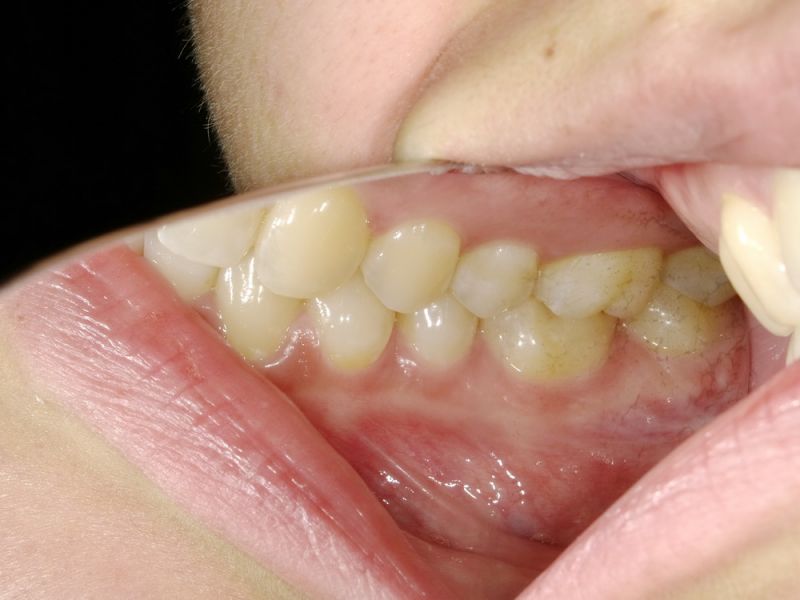

Ganz aktuell war die Patientin bei einer Hauszahnärztin, die auf die Idee kam der Patientin zwei Eckzahnfacetten im Oberkiefer zu installieren, mit dem Ergebnis, dass die Beschwerden der Patienti sich nochmals verschlechtert haben.

Auch hier einmal wieder mehr: Eine kurzentschlossene Therapie, ohne jede vorhergehende Diagnostik. Im zahnärztlichen Bereich eher üblich, als außergewöhnlich. Wir denken nur an die üblichen Geschichten vermeintlicher Erosionen, bei denn die Patienten am Tag 370 Liter Cola und 580 Yoghurts essen müssten, um die ph Werte zu realisieren, die für erosive Zahnsubstanzverluste Voraussetzung wären.

Das in Wirklichkeit unphysiologische okklusale Belastungen, hervorgerufen durch latente funktionelle Fehlbelastungen der Zahnoberflächen die Ursache von Vorschädigungen der Zahnhartsubstanzen sind, so dass dann tatsächlich schon das normale Zähneputzen zu Zahnsubstanzverlusten führen kann, geht dabei unter.